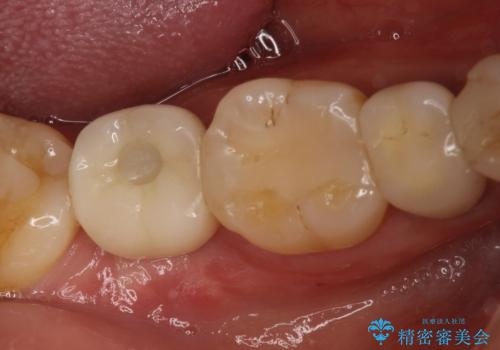

右下の奥歯を抜歯 インプラント治療による咬合回復

- 右下の奥歯をかぶせ物がとれたまま放置しているところに歯を入れたいとのことで来院されました。

精査すると保存が難しいため抜歯をして、インプラントを埋入、かぶせ物を装着する計画としました。

インプラント治療により、周りの歯を削ることなく咬合を回復することができました。